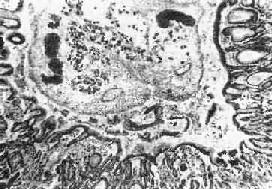

图19-13 肝华支睾吸虫病

胆管内可见虫体,胆管粘膜有腺样增生及炎症

1.肝 肉眼观,肝轻度肿大,尤以左叶为著,严重时在左叶被膜下即可见到因成虫机械阻塞而扩张的胆管分支,可能因左叶胆管较平直,易被童虫侵入之故。切面见肝内大、中胆管呈不同程度扩张和管壁增厚,胆管的直径可达3~6mm,壁可厚达0.5~3mm(图19-12)。胆管腔内充满胆汁,并含有数目不等的成虫。华支睾吸虫前端较细,后端钝圆,形似葵瓜子,虫体长约10~25mm,宽约3~5mm,柔软而半透明。在有大量虫体寄生的病例,解剖时轻压肝脏,即可见成虫由各胆管中鱼贯而出。镜下,根据感染虫数和感染持续时间的不同,病变可轻重不等。肝内胆管扩和,胆管上皮细胞呈不同程度增生,严重者上皮向管腔内呈乳头状增生,并可在粘膜下见多量的增生腺体,形成腺样结构(图19-13)。上皮细胞还常发生杯状细胞化生而分泌大量粘液。管壁有不等量淋巴细胞、浆细胞和嗜酸性粒细胞浸润。慢性病例则伴有明显的纤维结缔组织增生。部分病例汇管区的结缔组织也呈轻度增生,伴有上述炎性细胞浸润。在急性反应时汇管区的小胆管周围也可有多量嗜酸性粒细胞浸润,而肝实质细胞一般无明显改变。